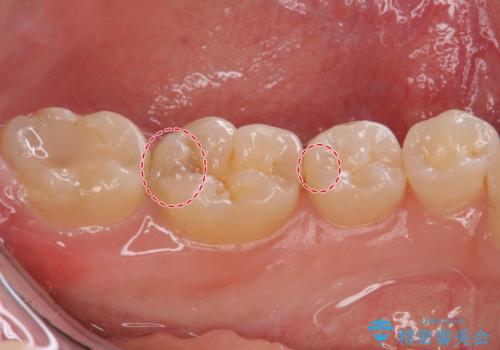

隠れているむし歯 セラミックインレーによる治療

- 2年ぶりの来院。メンテナンス時に虫歯が多数確認されました。

まずは虫歯の大きいところから治療を進めることになり今回は右下の奥歯の治療を行いました。